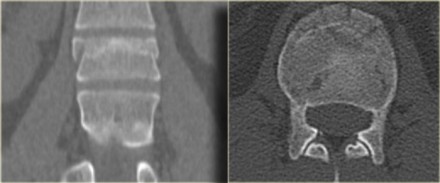

On the left images of a 31 year old male.

He was working on a roof, fell approximately 5 meters landing on his feet.

He complained of pain in left lower extremity and lower back.

First study the images, then continue reading.

On the x-ray there is a hyperflexion injury of L1 with

involvement of the anterior column and possible involvement of the

middle column.

The sagittal reconstructions of the CT demonstrate that the posterior

part of the vertebral body is of normal height, but there is some

involvement of the posterior part of the vertebral body.

There is debate on how to treat these patients and if there is any role of MRI in these cases.

If you are aggressive you could call this a two column injury, which would require stabilizing surgery.

If you are conservative you could call this an injury with only minor involvement of the middle column.

On the left a coronal reconstruction and an axial image at the level of the fracture.

Continue with the MR.

The MR images show bone marrow edema in the involved vertebral body, but no additional soft tissue injury.

Based on the fact that the MR did not show any additional findings, this patient was treated as having a single column injury.

Consultation with orthopedic surgery recommended conservative management with a TLSO brace.

Nowadays there is a tendency to treat these thoracolumbar injuries

conservatively, even if there is slight involvement of the middle

column.

The role of MRI in these cases is not clear yet.